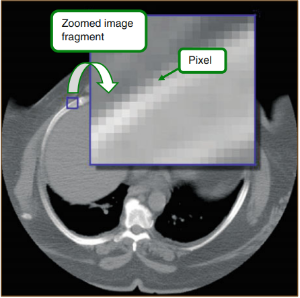

این موارد شما را برای مرحله بعدی در این سفر آماده کردهاند و این مرحله به بررسی نحوه کارکرد دایکام با تصاویر پزشکی میپردازد. بدون شک، تصاویر ویژگیهای شناخته شدهای دارند که از جمله آنها میتوان به عرض، طول و تعداد پیکسل اشاره کرد که میتوان آنها را در دیکشنری داده دایکام پیدا نمود و همانطور که پیشتر نیز یاد گرفتید، دایکام آنها را با استفاده از واقعیت مجازی ضمنی یا صریح رمزگذاری میکند. اما جالبترین ویژگی تصویر، همان خود تصویر است که توالی مقادیر پیکسلی میباشد و دایکام آن را در تگ داده پیکسلی استاندارد (vFE0, 0010)با استفاده از OB (برای پیکسلهای یک بایتی) یا OW (برای نمونه پیکسلهای دو بایتی) رمزگذاری میکند.